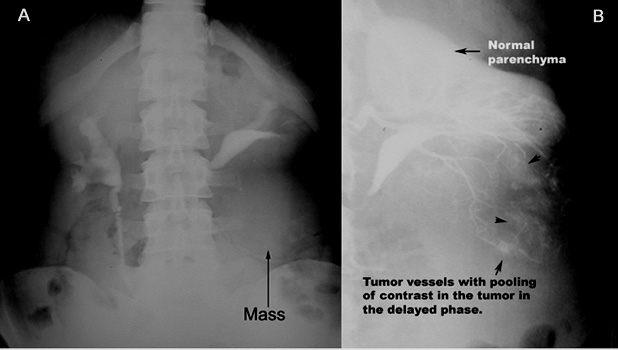

Angiogram

- Neovascularization

Renal Cell Carcinoma

- A: IVP shows mass in the lower pole of left kidney

- B: Angiogram showing neovascularization